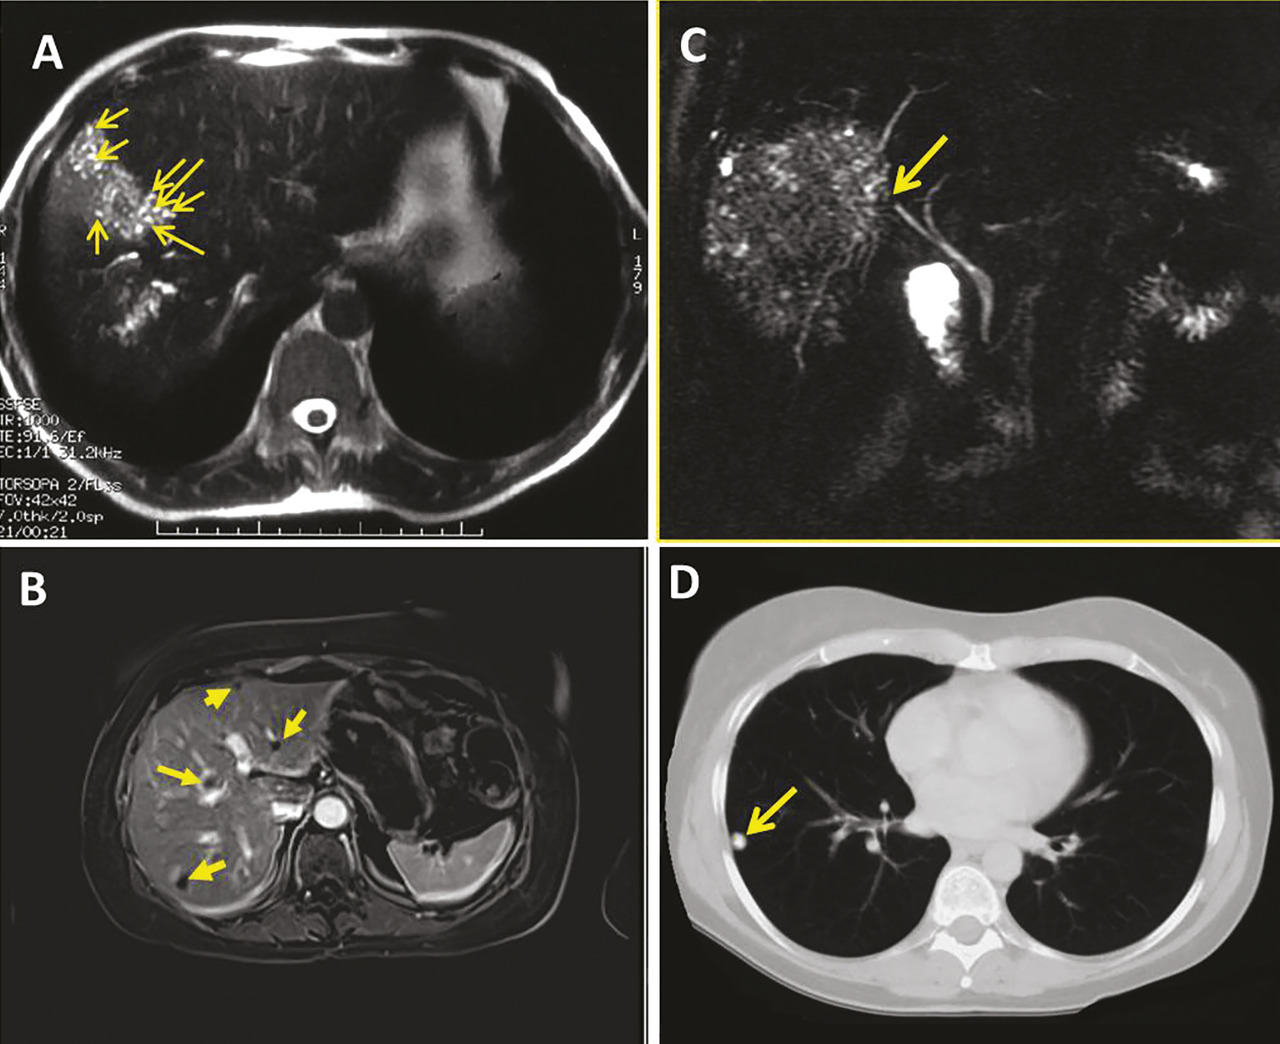

Imagerie par résonance magnétique

L’imagerie par résonance magnétique (IRM), qui méconnaît les calcifications, est cependant la meilleure technique pour analyser les contenus des foyers parasitaires.3, 14, 15 Les multiples vésicules parasitaires, infra­centimétriques, peuvent être visualisées en hypersignal en pondération T2 : l’image « en rayons de miel » ou en « grappes de raisin » est pathognomonique de l’affection ; l’identification des microkystes est associée à l’activité métabolique des lésions.19 L’IRM est complémentaire de la TDM pour apprécier les envahissements vas­culaires en particulier cave et sus-­hépatiques et l’extension de conti­guïté ; enfin, la cholangio-IRM est indispensable en cas de cholestase et de doute sur l’invasion ou l’obstruction des voies biliaires (fig. 5).

TEP-TDM

Une hyperconsommation du fluoro- désoxyglucose (FDG) à la périphérie des lésions en tomographie par émission de positons couplée à la tomo­densitométrie (TEP-TDM), bien qu’en réalité associée à la réponse immunitaire de l’hôte, est considérée comme le meilleur signe d’activité métabolique du métacestode (fig. 4).3, 15, 20 Cependant, pour une évaluation optimale, il est indispensable d’ajouter une mesure 3 heures après l’injection du FDG aux mesures faites habituellement 1 heure après injection.21